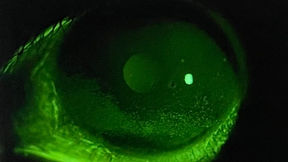

OCCHIO SECCO

Valutare l'Occhio Secco

Ghiandole di Meibonio